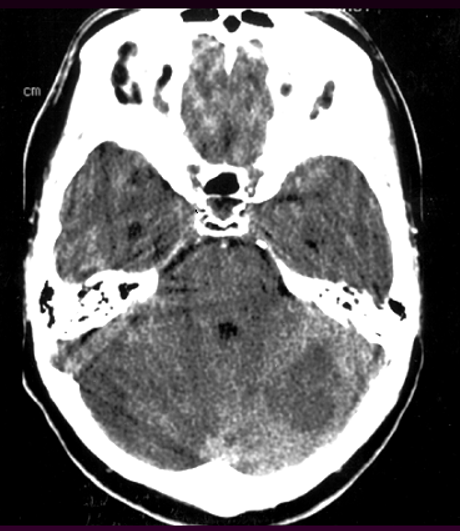

Tuần hoàn sau:

Từ các động mạch đốt sống tạo thành hệ sống-nền, có nhiều nhánh (các động mạch tiểu não, nhánh cầu não, động mạch não sau (PCA), động mạch thông sau. Tổn thương hệ động mạch này biểu hiện với:

- Các dấu hiệu thần kinh sọ não: III,IV,VI,VII, VIII…

- Các dấu hiệu tiểu não: thất điều

- Các dấu hiệu đường dài (long tract signs): liệt (nửa người đối bên hoặc liệt tứ chi), rối loạn cảm giác… đối bên tổn thương (dấu hiệu chéo)

Xuất huyết/ chảy máu

Xuất huyết trong não (nhu mô)

- Nguyên nhân: Phình mạch Charcot-Bouchard, Tăng huyết áp, Tự phát

- Xảy ra ở hạch nền, đồi thị, cầu não, tiểu não